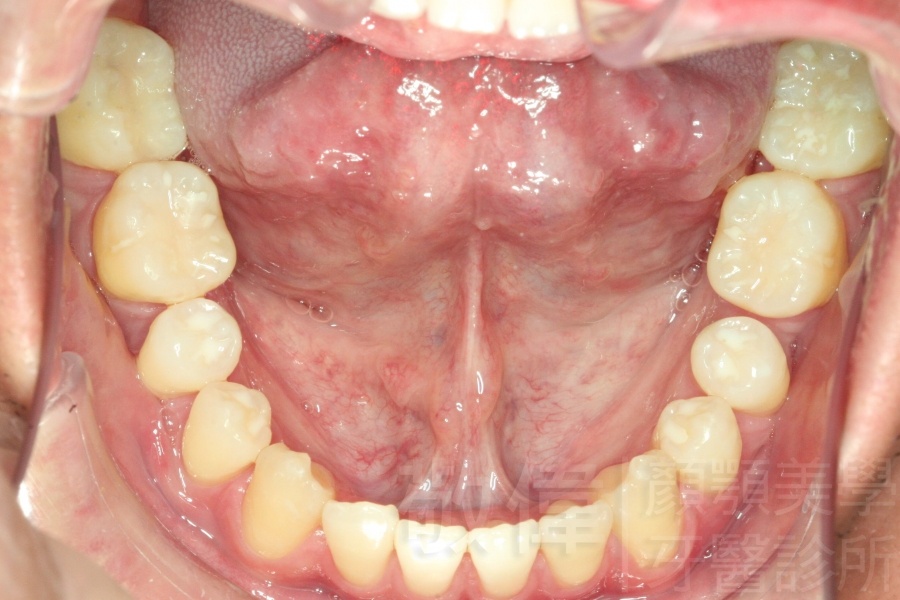

變臉矯正,原來戽斗妹跟大歪臉變成自信正妹

經由本院3D數影X光影像儀分析、與3D齒顎顏矯正技術,再配合口腔顎面正顎專科醫師施以正顎手術治療,雙方共同合作,使患者臉部外觀有很好的改善,大歪變小歪,產生了天南地北的大改變,她的人生也整個變得不一樣。

因為矯正與正顎手術的配合,使「戽斗妹」變成了「陽光正妹」,完全的改變了她的人生,在面對各種場合、與人交際都散發出自信微笑。所以,奉勸家長,如果小朋友有臉顎畸型的問題,應該考慮配合做這種簡單、安全、有效的正顎手術。

「3D齒顎顏矯正」,不止矯正您的牙齒,也會改變您的人生。「治療前」和「治療後」出社會的人生際遇一定會截然不同。